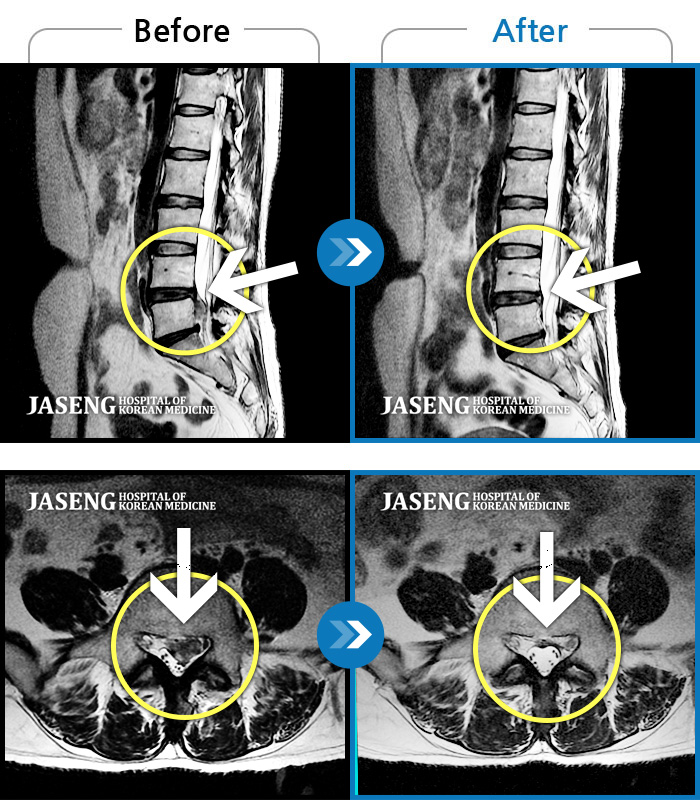

허리디스크

대전 · 김창연 원장

엉덩이의 왼쪽 부위 및 하지방사통이 심각하여 보행이 불가한 상태에서 내원하셨습니다.

촬영시기

2025.01.22 ~ 2025.08.09

2025.08.19